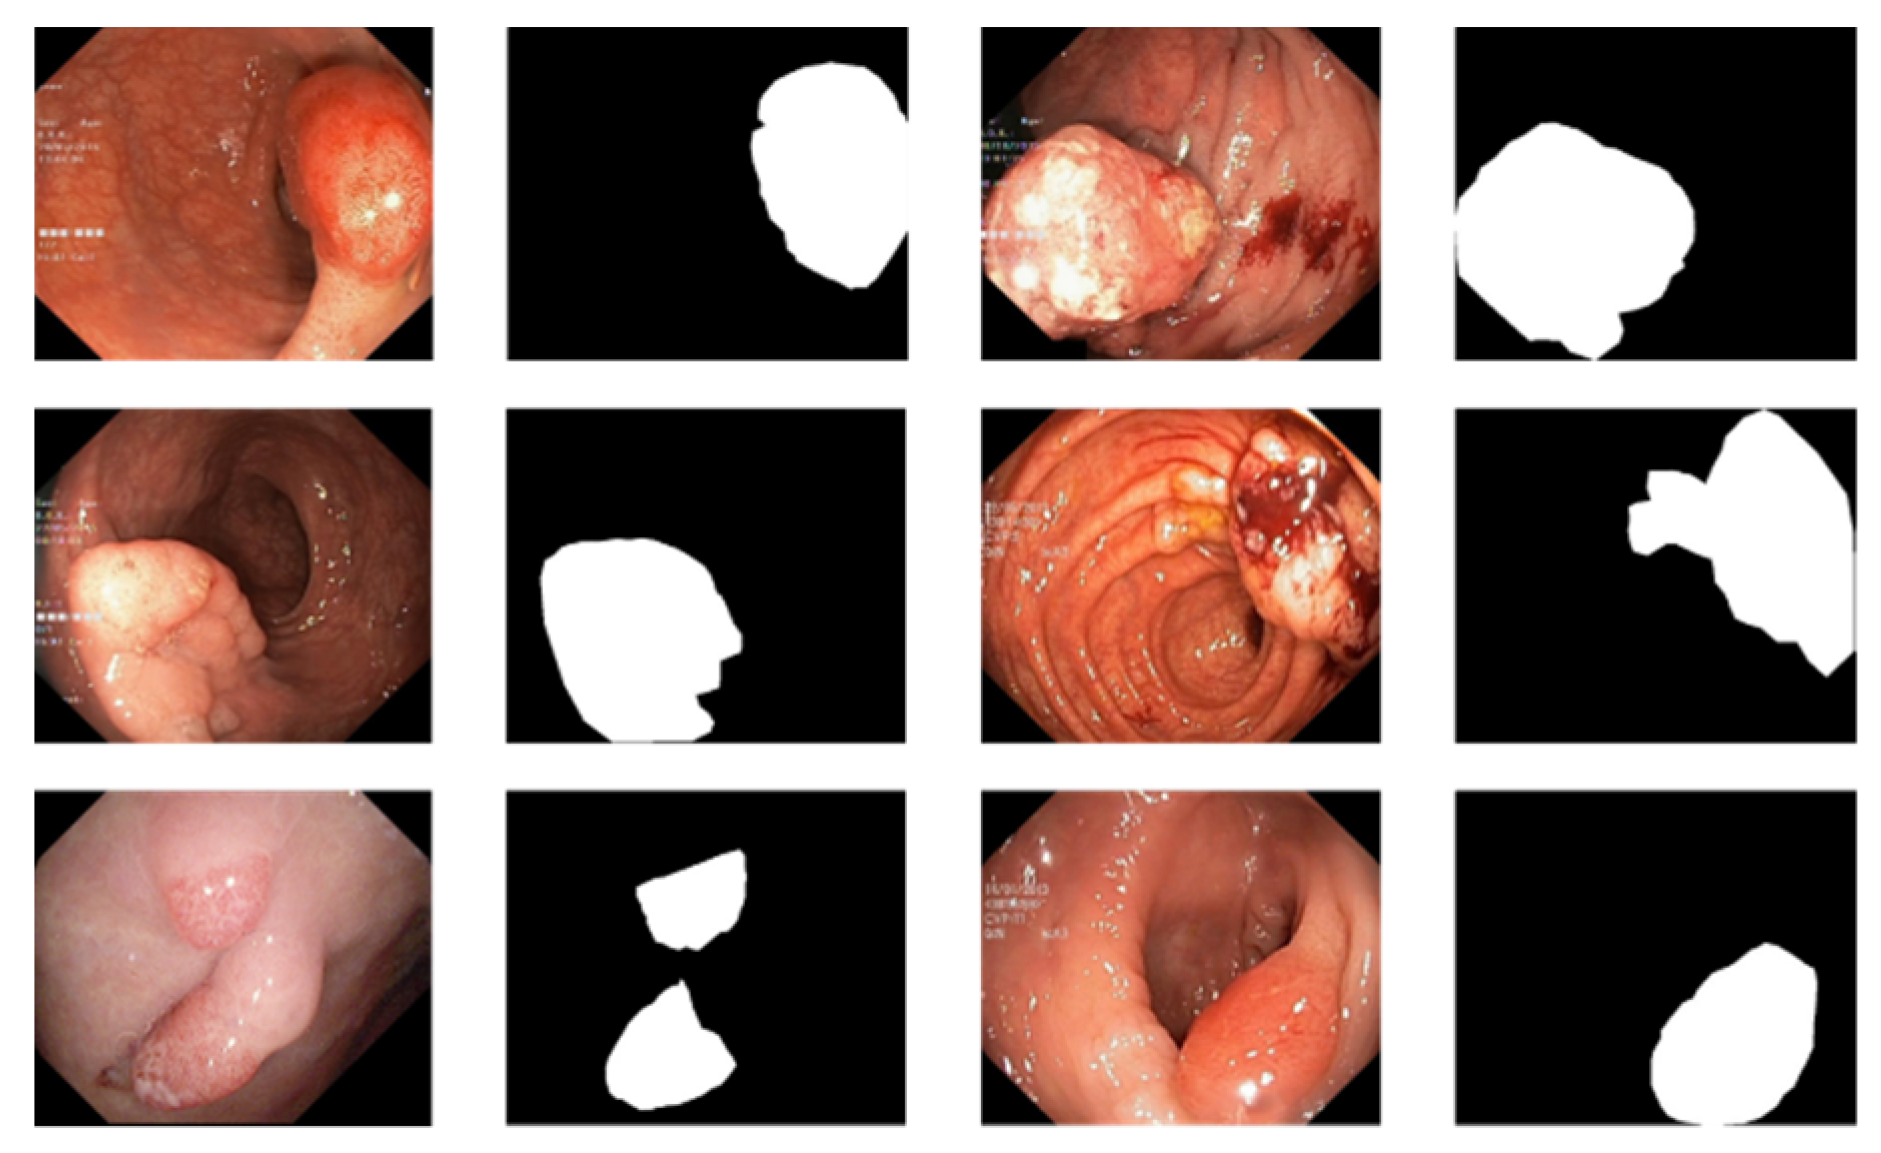

There are currently only a few public datasets of intestinal polyps available for model training and testing. Polyps exist in various shapes and colors as well as textures [11]. As shown in Figure 1, the minute difference between polyps and the normal ambient environment or partially diseased areas covering the feces is the main challenge in the detection of polyps. In this paper, we used the open datasets of Kvasir-SEG [12] and CVC-ClinicDB and performed relevant experiments

For the polyp image segmentation task, every pixel in the training image was labeled as either polyp or non-polyp. The evaluation of the PRAPNet was accomplished utilizing the Kvasir-SEG dataset and CVC-ClinicDB [17] dataset. The Kvasir-SEG dataset consists of 1000 polyp images and their corresponding mask maps annotated by specialist endoscopists from Oslo University Hospital, Norway. The CVC-ClinicDB dataset consists of 612 polyp images. Figure 1 shows example images from the Kvasir-SEG dataset and their corresponding templates. As the number of polyp pictures was too small, direct training would lead to overfitting. Thus, it was necessary to increase the number of polyp pictures in the training set; the number of Kvasir-SEG images was 11,000 and the number of CVC-ClinicDB images was 6732. Traditional data enhancement technology—namely, vertical flip, horizontal flip, 90 degrees clockwise rotation, translation, changing the image brightness, and Gaussian blur—was used to increase the training samples from the initial images. Of these images, 80% were randomly selected for the training, 10% were used for the validation, and 10% were used for the testing.

Figure 1. An example of polyp pictures from the Kvasir-SEG dataset, together with their accompanying masks. The first and third columns show the original image; the second and fourth columns show the accompanying masks.